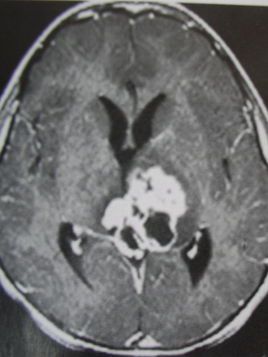

顱內生殖細胞瘤是臨床上比較少見的一種惡性腫瘤,發(fā)病率在3.5%左右,多見于青少年群體以及兒童,在老年人群以及幼兒中較為罕見,好發(fā)部位是鞍區(qū)以及松果體區(qū),在丘腦、基底節(jié)部位較為少見,生殖細胞瘤極易導致腦脊液散播種植,并對周圍的結構進行侵犯,早期精確、有效的診斷對于患者疾病的治療具有十分重要的意義。